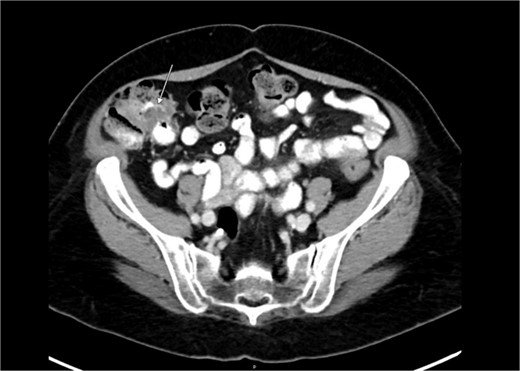

Preoperative abdominal computed tomography revealed a mass in the ascending colon (Fig. 1) and multiple nonspecific cystic lesions in the peritoneal cavity involving the abdomen and pelvis (Fig. 2). Normally, carcinomatosis would be suspected in a patient with mucinous adenocarcinoma of the colon. However, the radiographic findings were not definitive for carcinomatosis, and the history of abdominal ‘cysts’ 20 years previously further confused the situation. The differential at the time included malignant carcinomatosis, benign endometriotic cysts, and cystic peritoneal reaction to previously placed intraperitoneal hernia mesh. Carcinoembryonic antigen measured 0.8 ng/mL.

Computed tomography abdomen/pelvis—arrows indicate peritoneal cysts.